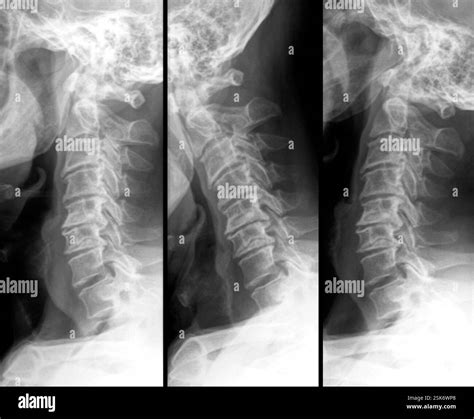

Waking up with a stiff neck is something most of us experience occasionally, but when that pain becomes a chronic companion, it may be a sign of deeper structural changes in your spine. One of the most common culprits for persistent neck discomfort and radiating pain is the development of bone spurs in neck regions, medically referred to as cervical osteophytes. These bony projections, which grow along the edges of the bones in your spine, are often the body's attempt to stabilize the area following age-related wear and tear. While they are not always painful, they can cause significant distress if they press against nerves or the spinal cord, leading to a condition known as cervical spondylosis.

Bone spurs in neck areas are essentially smooth, hard bumps of extra bone that form on the vertebrae. They are not “spurs” in the sharp, pointy sense; rather, they are rounded growths that develop in response to friction and pressure. As we age, the cushions between our vertebrae—the intervertebral discs—begin to dehydrate and shrink. This reduces the space between the bones and creates instability.

To compensate for this instability, the body naturally attempts to stabilize the spine by increasing the surface area of the vertebrae. It lays down additional bone, which eventually turns into these spurs. While the intent is to protect the spine, the result is often the opposite: the spurs can narrow the space available for nerves to exit the spinal canal, leading to compression, inflammation, and pain.

A doctor will likely use diagnostic imaging such as X-rays, MRIs, or CT scans to visualize the bone spurs. An MRI is particularly helpful for determining if the spurs are compressing nerves or the spinal cord, which guides the next steps in your treatment journey.